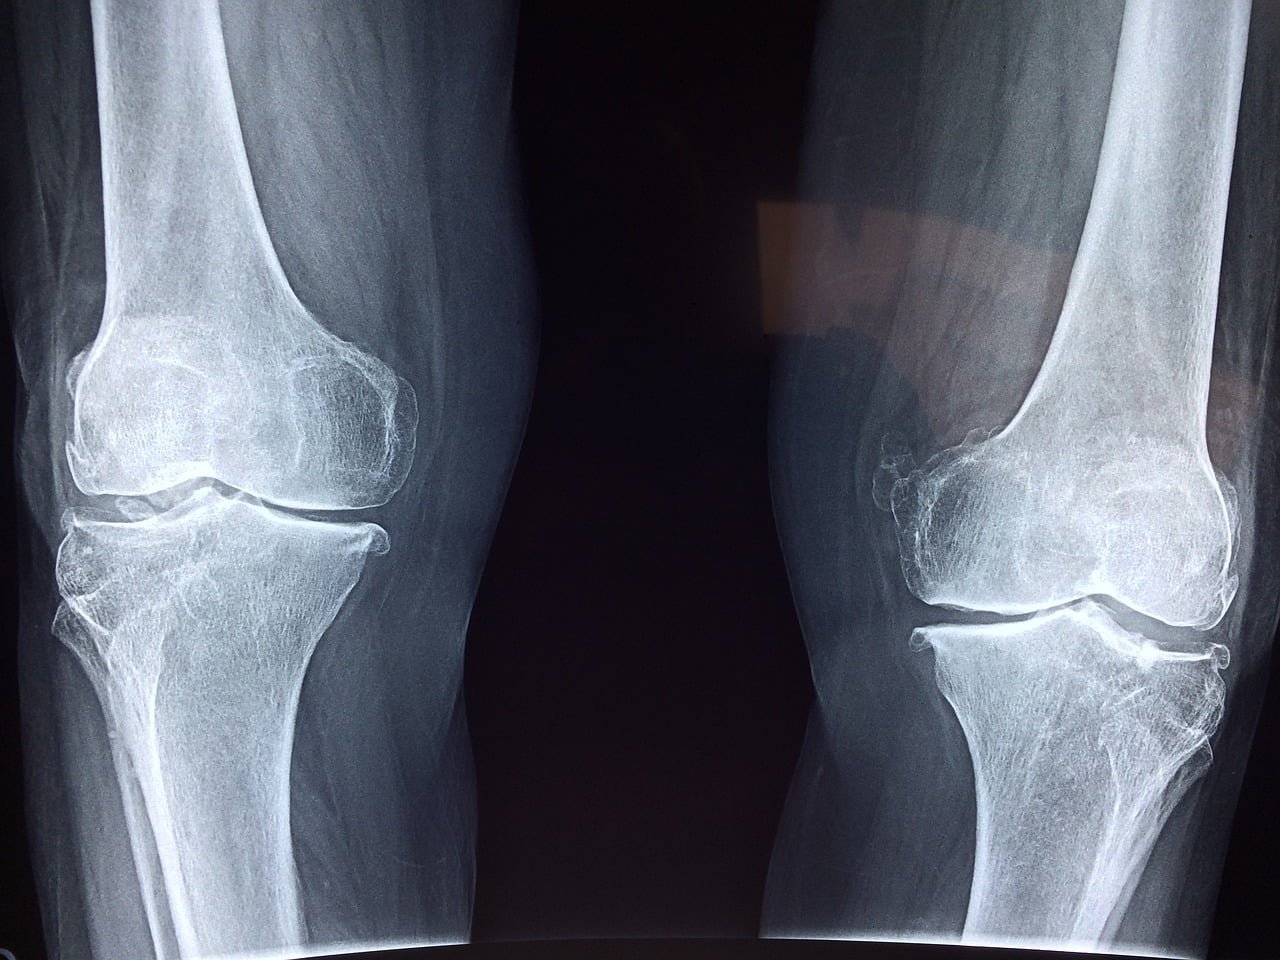

– الأشعة السينية. قد يقترح الطبيب أولاً إجراء أشعة سينية، والتي يمكن أن تساعد في اكتشاف كسور العظام وأمراض المفاصل التنكسية.

طرق التشخيص:

تشمل التقنيات التشخيصية الأشعة السينية والرنين المغناطيسي والفحص السريري. الاستشارة مع طبيب عظام متخصص ضرورية للتحقق من التشخيص.